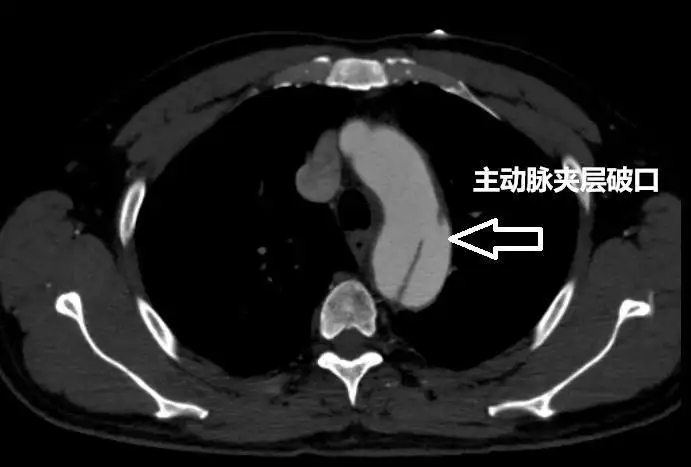

“进一步检查发现,患者王先生当时的主动脉从左锁骨下动脉一路撕裂至左髂动脉,累计长度已近40厘米,影响到多器官供血血管。”卢惟钦说。

▲患者术前主动脉夹层检查影像 受访医生供图

主动脉是人体最粗大且直接连接心脏的血管,压力极高。而所谓主动脉夹层,实际上是一种常见的心血管疾病,但危险性极高。卢惟钦告诉红星新闻:“主动脉夹层即血管壁内膜撕裂,血液冲入中层形成‘真假两腔’,一旦外膜破裂会引发大出血,死亡率极高。”

卢惟钦介绍,主动脉夹层是一种极为危险的心血管疾病,通常又被称为“血管炸弹”。他用通俗的话向记者解释,人的血管实际分为三层,当血压过高时,就可能导致血管中薄弱的一层破损,而血液一旦涌入破损的一层,就会与未破损血管层形成夹层,也即主动脉夹层。